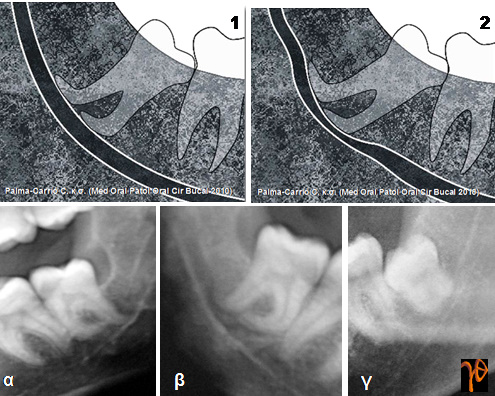

Στις εικόνες που ακολουθούν υπενθυμίζονται κάποιες από αυτές τις περιπτώσεις στις οποίες θα πρέπει να δίνεται ιδιαίτερη προεγχειρητική και χειρουργική προσοχή:

Εικόνα 1. Απόκλιση των ριζών [Σχέδιο (1) και Ακτινογραφίες (α) και (β)], Στένωση του Πόρου [Σχέδιο (2) και Ακτινογραφίες (β) και (γ)]